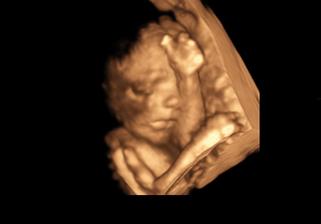

Nasa malinka v 24tt

@bambulka12 toto ako sa ukazala bol chvilkovy zazrak....inak v kuse obe ruky na tvari 🙂

@bambulka12 a diky som zabudla 🙂 no doktor vravel, ze aspon na chvilku by mohla ruky dat prec a to tak dve minuty boli z celeho 3D 🙂